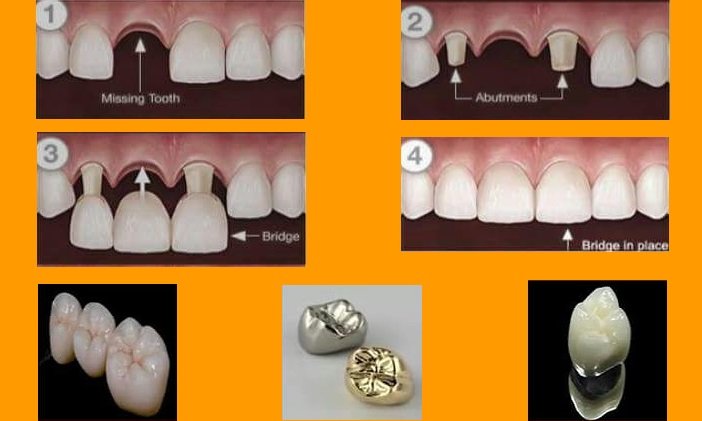

Fillings which are materials used to fill cavities in the teeth and crowns which slip over...

Fillings, which are materials used to fill cavities in the teeth, and crowns,...